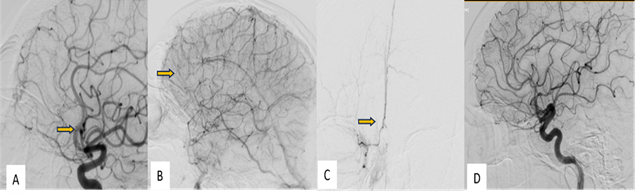

After a few days the patient was

admitted for embolization under GA. Right CFA access was taken with 6 F short

sheath using Envoy 5F guide catheter and wire combination, right ICA gram was

obtained. 2mg infusion of Nimodipine was started slowly. Using marathon

microcatheter and mirage microwire combination, right ophthalmic artery was

cannulated. Fistulous branches were cannulated with marathon micro-catheter

taken over mirage 0.08” microwire till the dural AVF nidus.

No early draining veins or fistulous

connection was observed despite super selective catheterization.

Super-selective cannulation of the right ACA was done however no early draining

veins were found. Normal filling of intracranial circulation was seen (Figure

3 A-C). Contralateral ICA injection confirmed spontaneous closure of the

DAVF (Figure 3D).

Figure 3: (A), (B) Selective digitally

subtracted angiography images in arterial and venous phases through the right

Internal Carotid Artery did not show any fistula at the previously documented

site (arrow)

(C) - Superselective digitally

subtracted angiography images through the branches of anterior cerebral artery

did not any fistula (arrow)

(D)- Selective digitally

subtracted angiography images through the contralateral (left) Internal Carotid

Artery did not show any fistula at the previously documented site